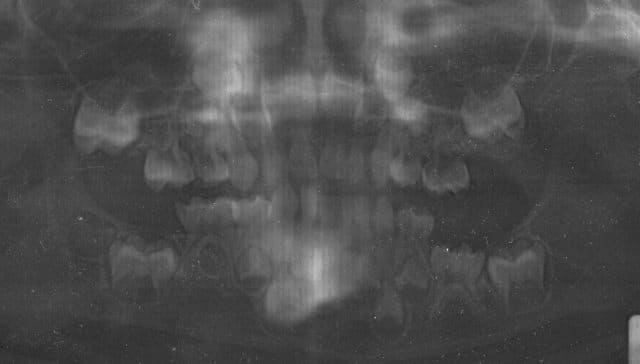

il y a neuf mois dans une petite consultation de routine chez un petit Lukas de 3ans et 5mois, je constate que la 75 n'est pas en place, à l'orthopanto... la 75 est bien là mais elle semble retenue. suite à l'avis de l'orthodontiste: wait and see.

en pièce jointe vous verrez la radio panoramique prise cette semaine, à l'age de 4ans et 2 mois donc (désolé j'ai pas pu faire mieux en la scannant), la 75 n'a pas bougé et de plus le germe de la 35 n'est pas visible alors que ceux de 45 47 37 (de date d'apparition comparable) le sont.

La 75 semble ankylosée et ne fera donc jamais son éruption .Quant à la 35 il y a peut être agénésie mais il est trop tôt pour se prononcer car le germe peut être en retard de formation.

Traitement: attendre et extraire la 75 à un age où l'enfant sera coopérant (vers 10 ans). S'il ne coopère pas faire une AG.Pour le reste ce sera de l'ODF.